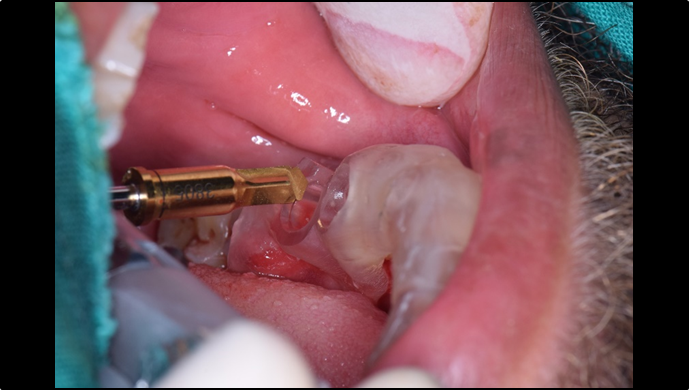

Clinical case: Extraction, immediate placement & loading using

R2GATE solution in aesthetic zone

- Courtesy of Dr. Jong-Cheol Kim, Korea-